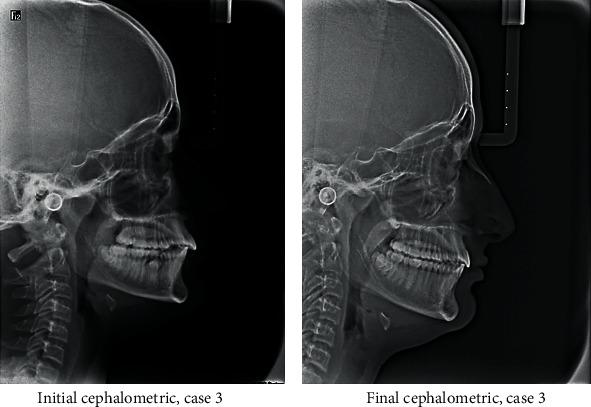

Distalization is a conservative method that is utilized in orthodontics to gain space by moving posterior teeth distally. It may be combined with other space gaining strategies, such as expansion, or can be used alone. Many methods have been used for distalization. These methods differ significantly in their place, whether to be extraoral or intraoral, site of action in upper and/or lower arch, and cooperation needed by the patient if it is removable or fixed. This review illustrates some of the most commonly used methods for distalization with a brief presentation of three cases that incorporated successful distalization techniques.

远中移动是正畸治疗中一种保守的方法,通过将后牙向远中移动来获得间隙。它可以与其他增加间隙的策略(如扩弓)相结合,也可以单独使用。已经有许多方法用于远中移动。这些方法在其位置(口外或口内)、在上颌和/或下颌牙弓的作用部位以及如果是可摘或固定矫治器时患者所需的配合方面有很大差异。本综述阐述了一些最常用的远中移动方法,并简要介绍了三个采用成功远中移动技术的病例。